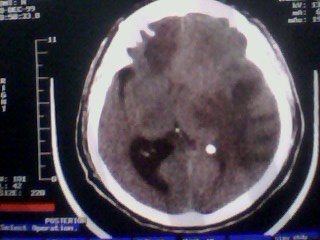

以下是引用随光逐影在2010-1-7 14:49:00的发言:[br]1)结合病史,考虑多发性脑转移瘤可能性大;建议行ct增强扫描检查。2)大脑镰下疝。3)脑积水。